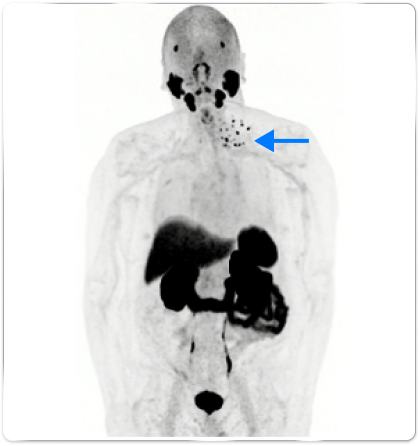

Patient B

Anterior whole body PYLARIFY PET MIP showed uptake in multiple left lower-cervical and supraclavicular lymph nodes (blue arrow)

In patients with similar profiles, PYLARIFY identified differences in extent of disease, guiding treatment changes

- Treatment with IMRT to lymph nodes + ADT

- Post-radiation PSA levels dropped to 0.04 ng/mL